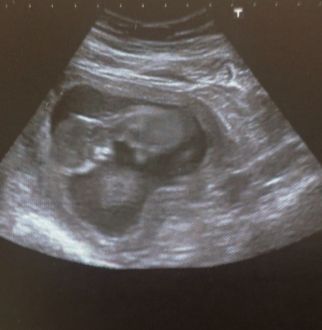

Echo des 12 sa

Petit compte rendu de mon rendez-vous!!

Ma petite crevette va bien!! Il mesure 6,2 cm, et il est déjà hyper actif (oui oui il bougeait tellement que la femme arrivait pas a faire une photo net lol) du coup elle ma donné un autre rendez vous car elle a pas pu voir tout ce qu'elle voulait voir!!